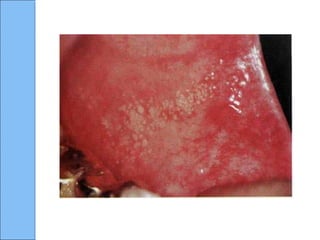

Gránulos de FordyceGránulos de Fordyce

CLÍNICAMENTECLÍNICAMENTE

◦ Múltiples lesiones papulares

◦ De color blanco amarillento

◦ A menudo aparecen en agregados o

arreglos concluyentes

◦ Más frecuente en mucosa bucal y borde

rojo del labio